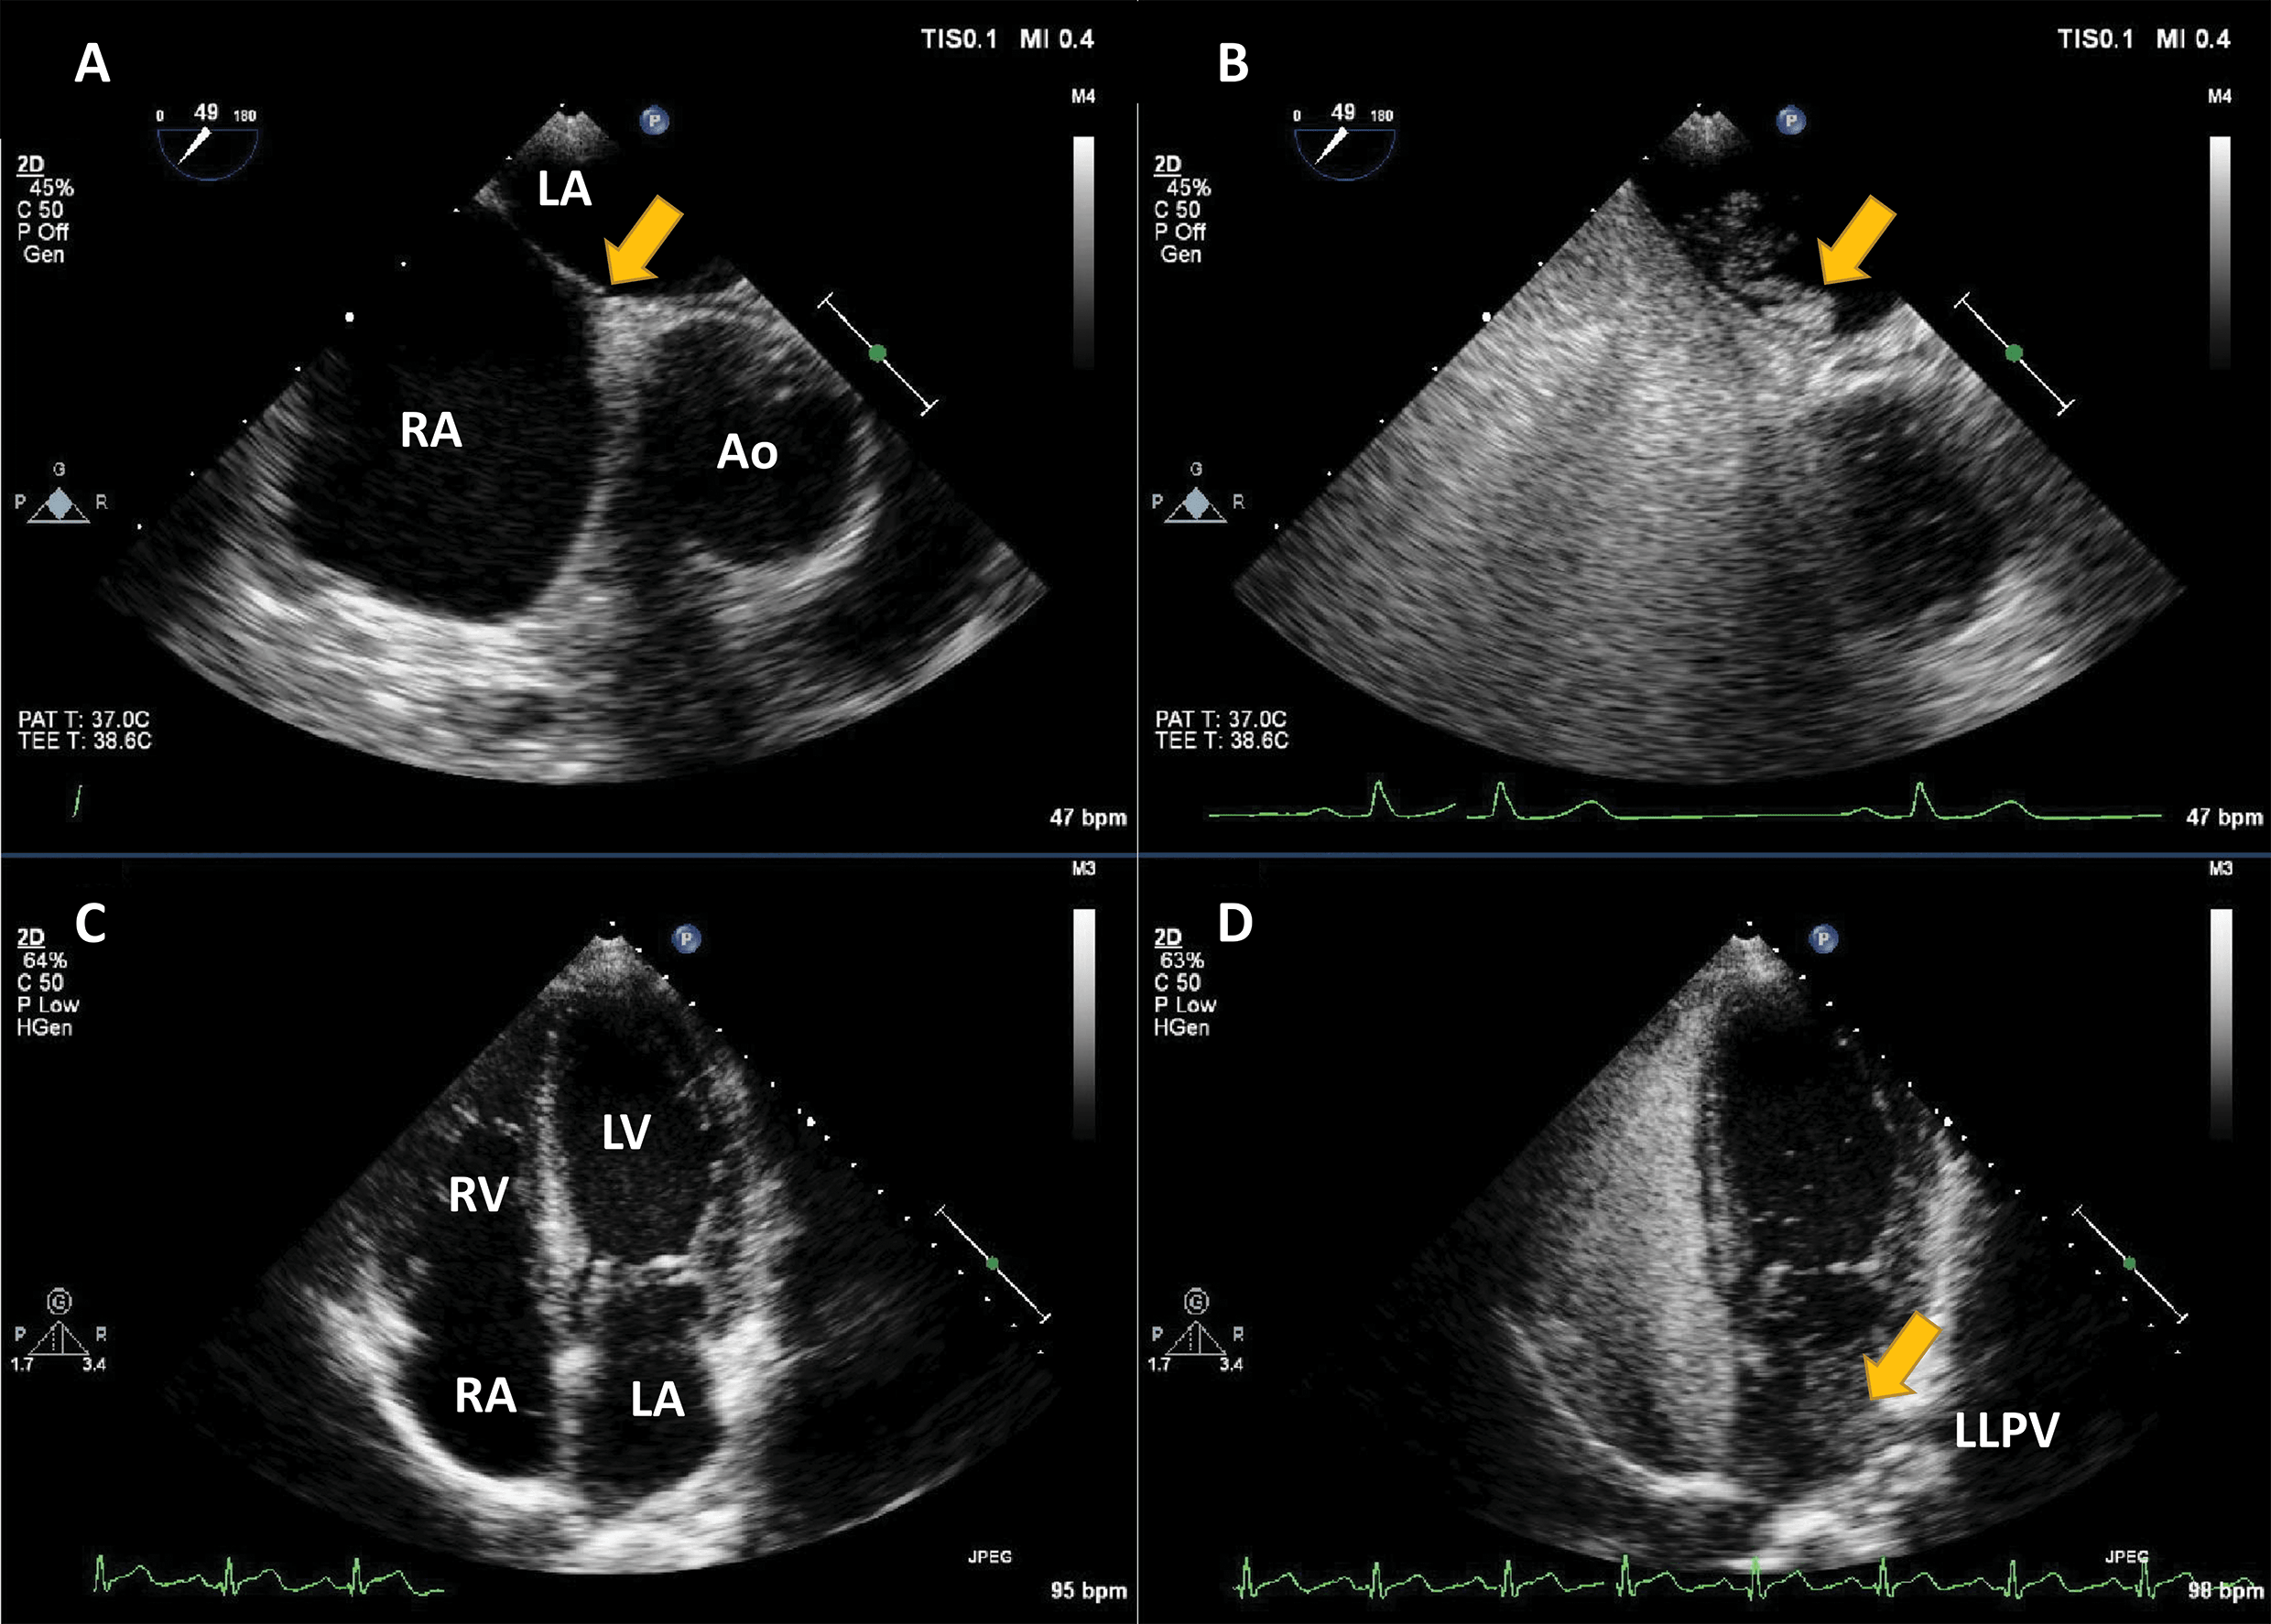

Fig. 1.Agitated saline injection for the detection of right-to-left shunts. (A,B) Example of intracardiac right-to-left shunting through a patent Foramen Ovale; transoesophageal echocardiography in mid-oesophageal position at 45°. The right atrium (RA), left atrium (LA) and interatrial septum at the level of the fossa ovalis are seen (arrow). After the infusion of agitated saline in a peripheral vein, a thick cloud of bubbles is seen passing through the patent foramen ovale (PFO) (arrow). (C,D) Right-to-left shunting through an intrapulmonary shunt, detected with transthoracic echocardiography, apical 4-chambers view. All four cavities are visualised. After the infusion of agitated saline in a peripheral vein, the right cavities are completely opacified. Seven heart cycles after the appearance of contrast in the right heart, a thick cloud of bubbles is seen in the LA (arrow), coming from the left lower pulmonary vein (LLPV). Source: personal collection.